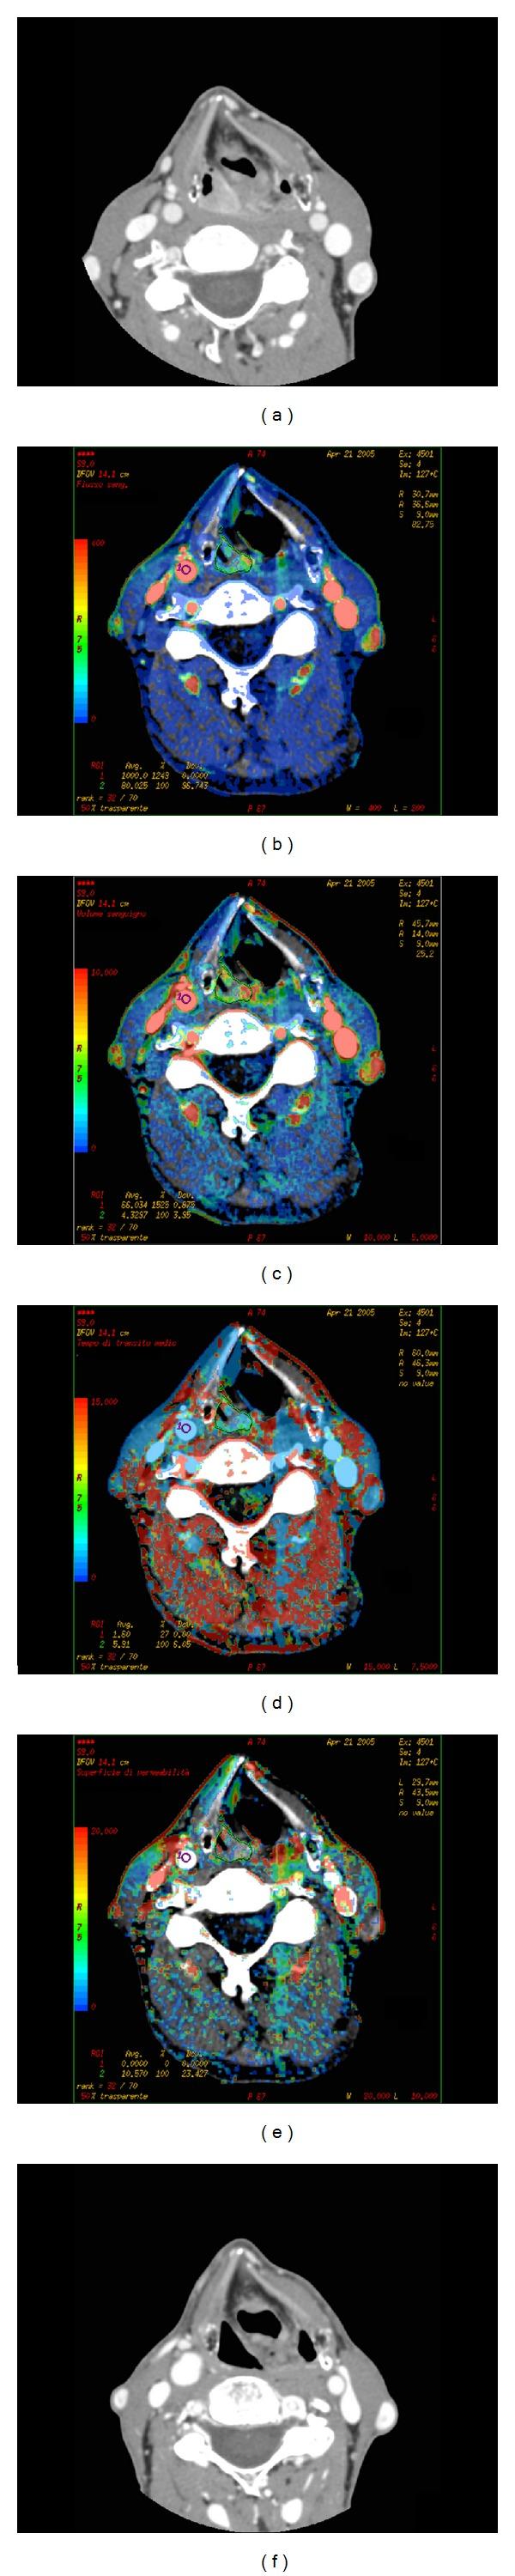

This review aims to summarize the technique and clinical applications of CT perfusion (CTp) of head and neck cancer. The most common pathologic type (90%) of head and neck cancer is squamous cell carcinoma (HNSCC): its diagnostic workup relies on CT and MRI, as they provide an accurate staging for the disease by determining tumour volume, assessing its extension, and detecting of lymph node metastases. Compared with conventional CT and MRI, CTp allows for obtaining measures of tumour vascular physiology and functional behaviour, and it has been demonstrated to be a feasible and useful tool in predicting local outcomes in patients undergoing radiation therapy and chemotherapy and may help monitor both treatments.

本综述旨在总结头颈部癌CT灌注(CTp)技术及其临床应用。头颈部癌最常见的病理类型(90%)是鳞状细胞癌(HNSCC):其诊断检查依赖于CT和MRI,因为它们通过确定肿瘤体积、评估其范围以及检测淋巴结转移为疾病提供准确分期。与传统CT和MRI相比,CTp能够获取肿瘤血管生理学和功能行为的相关测量值,并且已被证明是预测接受放疗和化疗患者局部预后的一种可行且有用的工具,还可能有助于监测这两种治疗。